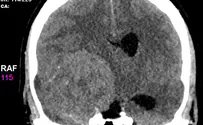

כירורג הילדים נתקע בשלג, מנהל מחלקת הכירורגיה למבוגרים בהדסה הר הצופים ניתח את הילד שנזקק לניתוח דחוף.

הצעיר הוכנס לניתוח ראש חירום כאשר נשקפת סכנה מיידית לחייו. "לרגע חששנו שאנו מאבדים אותו והוצא ממנו גידול ענק".